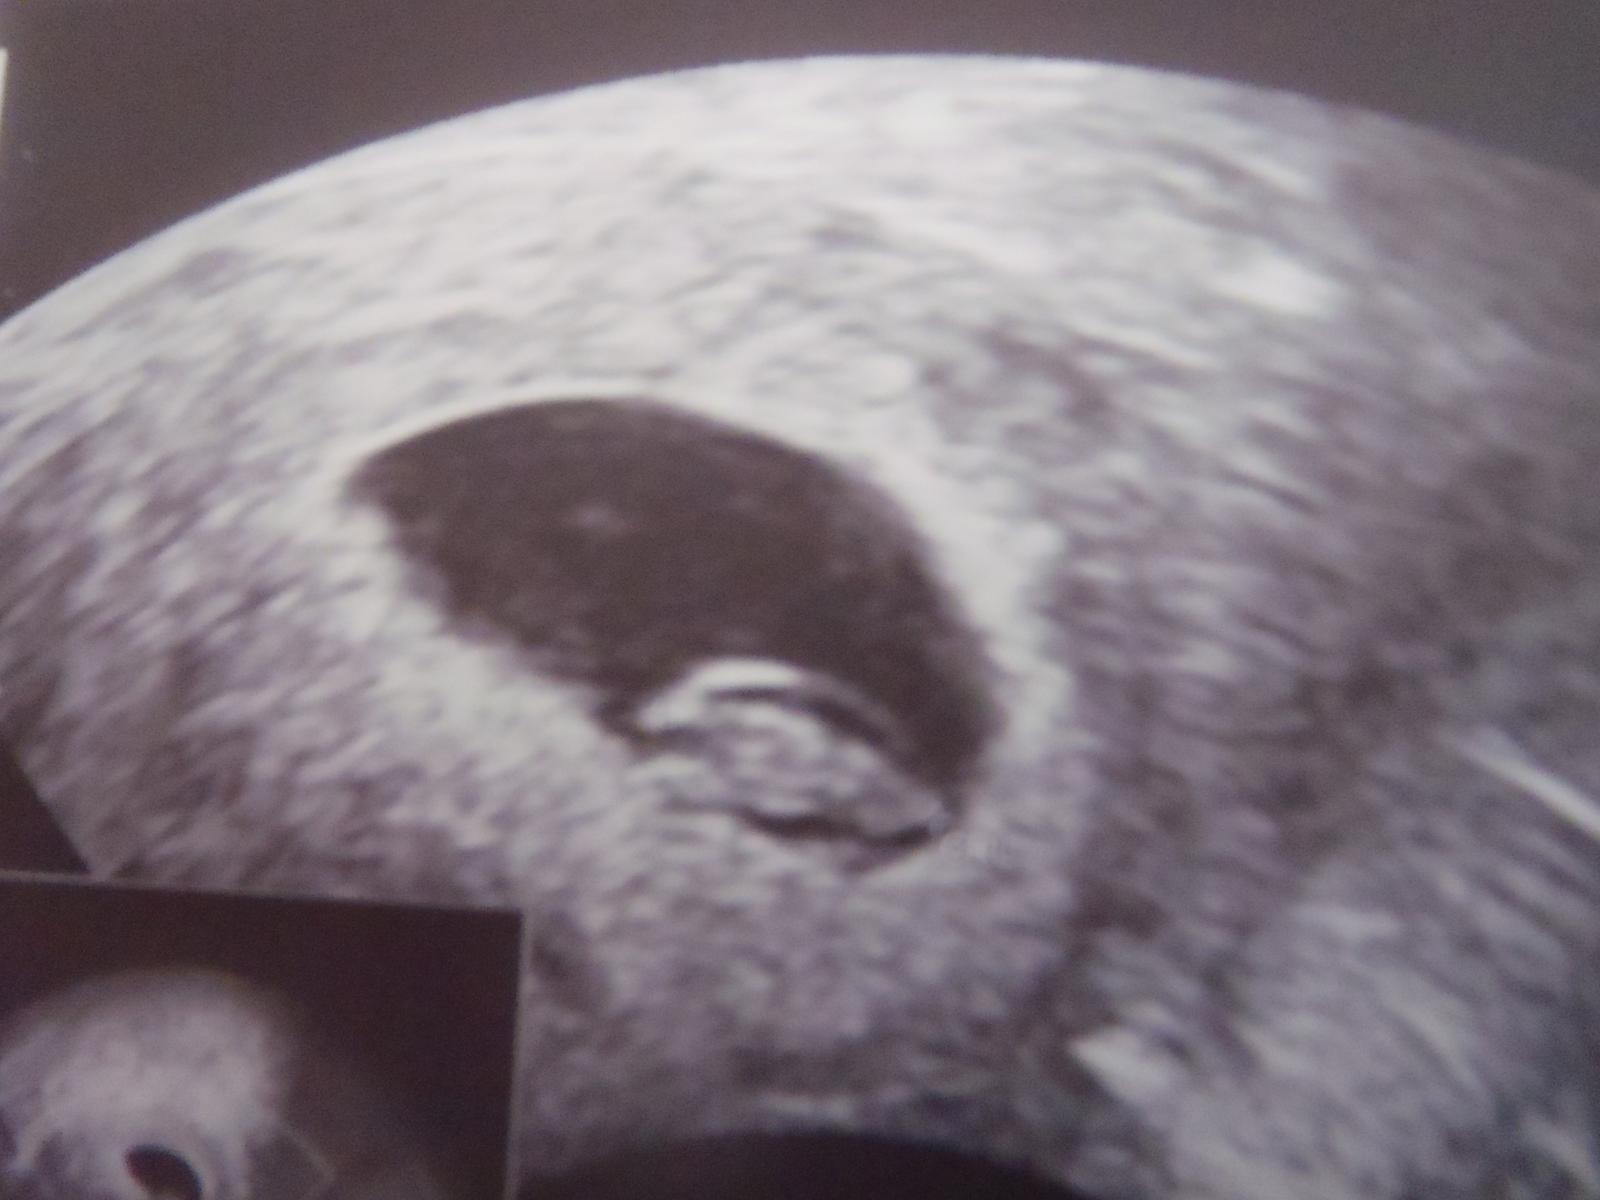

Ahojky, tak zítra mě čeká první UZ. Jsem s toho nervozní a dr. max test mě moc nepodpořil, pač byl slabší než ty minulé mama, ale snad je to jen výrobcem. Příznaky taky téměř žádné, jen prsa, šimrání a nervozita.

Ale věřím, vím, že tam bude být srdíčko !

@zelvicka111 🙂 tak tedy ještě jednou moc gratuluji 🙂 krásná fotečka krása 🙂

@zelvicka111 tak obrovská gratulace, nádhera 😉 😀